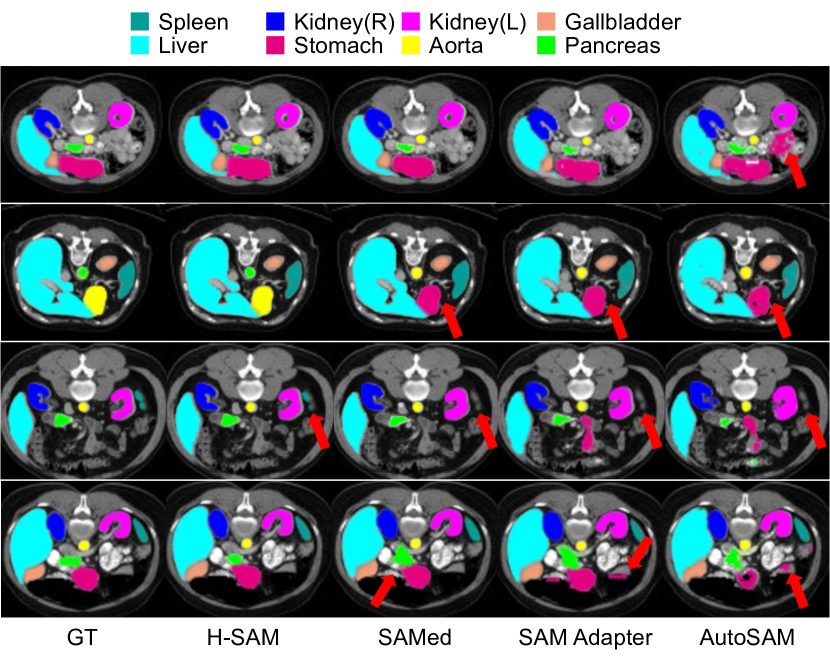

Appendix C Visualization

C.1 Zoom-in analysis

As shown in Figure 6 is the zoom-in visualization of H-SAM results against other SAM prompt-free variants. On the Synapse multi-organ CT dataset, H-SAM performs precise segmentation for small-scale organs. The pancreas marked as yellow in the figure is represented in a small region. SAM Adapter and AutoSAM provide a multi-organ segmentation with noise. While SAMed outputs a result with lesser noise, it is also confused by the shape of the organ. H-SAM outputs a perfect result with the correct shape and no noise.

C.2 Visualization on Synapse dataset

As shown in Figure 7, we present the visualization of semantic segmentation predictions on the Synapse dataset. Compared to ground truth, H-SAM performs promising results with both multiple organs (up to 8) and fewer organs.

Refer to caption

Figure 6: The zoom-in analysis of H-SAM results against other SAM prompt-free variants. H-SAM performs precise segmentation for small-scale organs.

Figure 7: Visualization of semantic segmentation predictions on the Synapse dataset. First and fourth columns: raw image. Second and fifth columns: ground truth. Third and sixth columns: prediction.